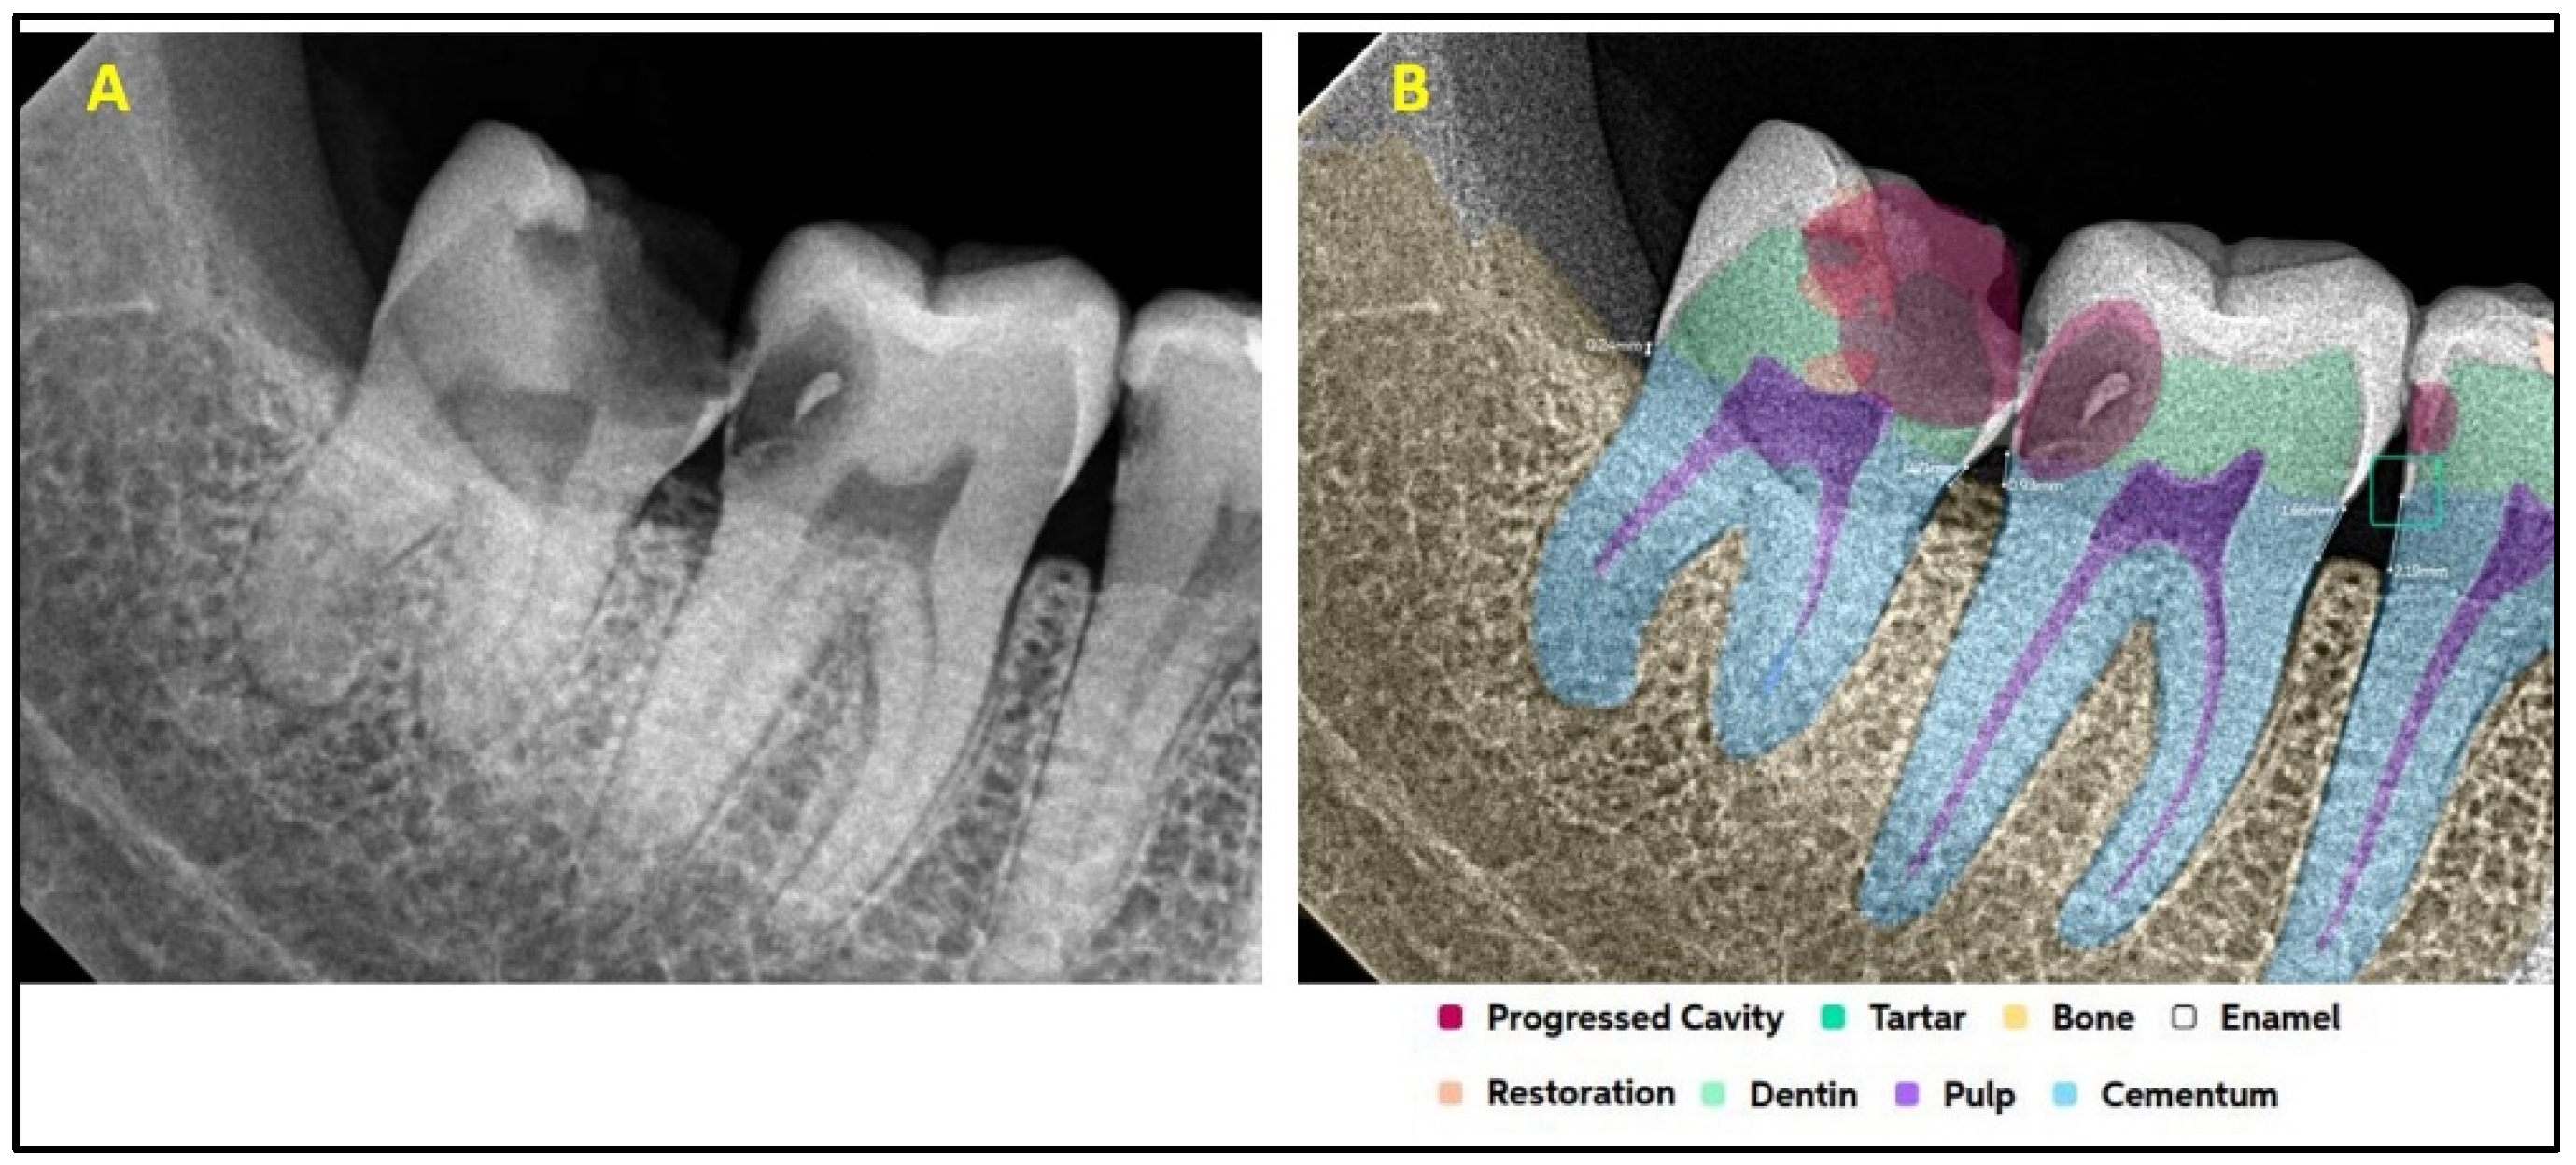

2.2. AI Software Architecture